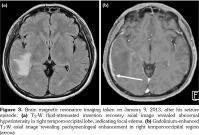

A 43-year-old male patient complained of right ear fullness that persisted for two years; he did not have type II diabetes mellitus, hypertension, or cholesteatoma. He was diagnosed to have otitis media with effusion; status post tympanocentesis was performed at another hospital at three different times; however, he suffered relapse soon after each treatment procedure. He then visited local medical doctors several times for tympanocentesis. In August 2011, he developed right hearing impairment for which he visited our hospital. An ear-nose-throat specialist confirmed right severe mixed hearing loss by pure tone audiometry (Figure 1). Mastoid computed tomography (CT) revealed abnormal soft tissue infiltration in his right middle ear cavity and right mastoid process with bony destruction (Figure 2). He received right tympanomastoidectomy in September 2011. His mastoid cavity was filled with granulation tissue and pus. His pathology report showed rich plasmacytoid cell infiltration. In the following two years, the patient did not visit our hospital, but he received several treatments for his ear from local medical doctors. His hearing, however, did not improve. Furthermore, the patient experienced an episode of seizure in January 2013. Magnetic resonance imaging of the brain revealed T2 hyperintensity and leptomeningeal enhancement (Figure 3), which indicated inflammation of the central nervous system. At this point, he revisited our hospital. Mastoid CT revealed abnormal soft tissue infiltration in his right middle ear cavity and right mastoid process with bony destruction. Hence, right modified mastoidectomy was performed and pulsatile granulomatous mass over his right mastoid cavity was found. His pathology report revealed plasma cell granuloma; however, the possibility of plasmacytoma was excluded on the basis of immunostaining results. In addition, it revealed positive IgG4 stain, with 59 IgG4- positive plasma cells in a high-power field (Figure 4). The percentage of IgG4-positive plasma cells in the field was approximately 45%. This finding led to the diagnosis of IgG4-RD, after which we initiated immunotherapy with cyclophosphamide and rituximab from April 2013 onward. Subsequently, the patient’s symptoms subsided and he did not require as frequent tympanocentesis as he did earlier. The erythrocyte sedimentation rate, IgG, and IgG4 levels also decreased after the treatment. The follow-up mastoid CT revealed remission of the pseudo tumor in his right middle ear cavity (Figure 5). A written informed consent was obtained from the patient.